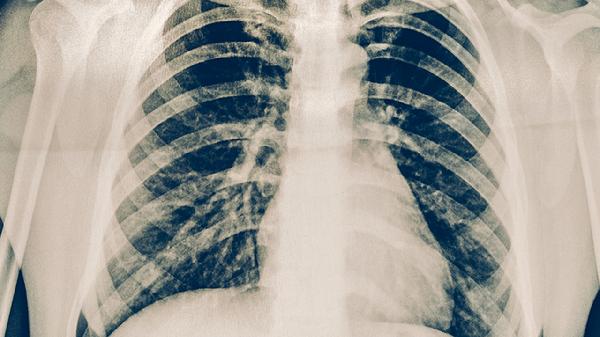

极少数情况下,鼻病毒感染可能引起病毒性肺炎,多见于免疫功能严重受损者。这类患者可能出现持续高热、呼吸急促、血氧饱和度下降等表现,需通过胸部CT和病原学检测确诊。早产儿、未接种疫苗的婴幼儿、长期使用免疫抑制剂的患者属于高风险人群,需加强防护。